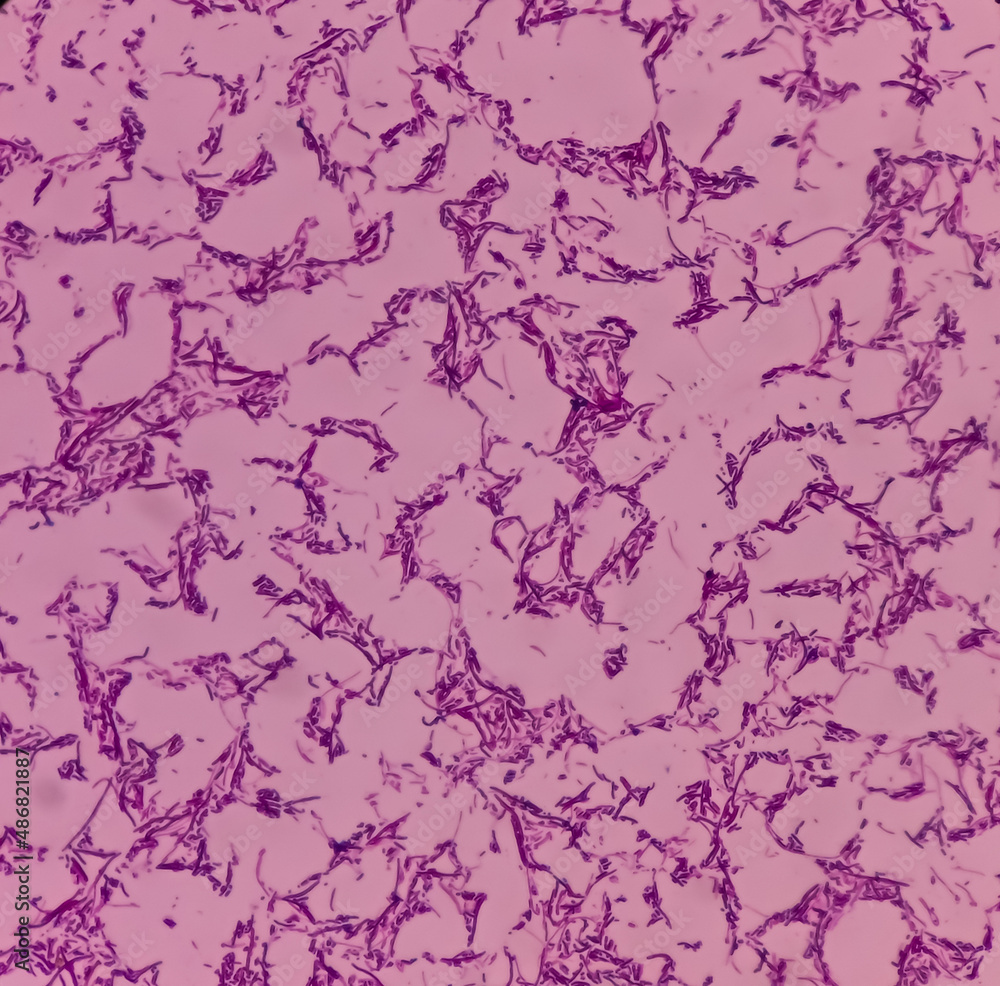

Salmonella Under Microscope 1000X . Generally speaking, it is theoretically and practically possible to see living and unstained bacteria. It is recommended to use a compound microscope with at least 1000x magnification. To identify bacteria under a microscope, a good quality microscope with high magnification is essential. A binocular microscope is also preferable as it is easier to use and more comfortable on the eyes. Salmonella images (from the strain that causes typhoid fever) captured under the microscope at various magnifications. The answer is a careful “yes, but”. Salmonella infection (salmonellosis) often results in diarrhea, fever (because of inflammation) as well as abdominal cramps that occur 1 to 3 days after infection. This bacterium is a major cause of pneumonia, meningitis, and other respiratory infections. It can be observed under the microscope in chains or pairs (diplococci).